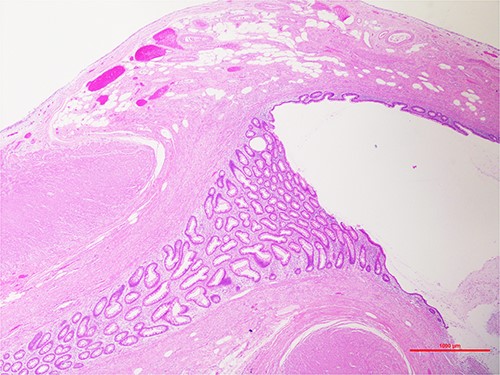

The procedure found an inflamed appendix with a 3-mm nodule on the tip of it (Fig. 1). No lymphadenopathy was seen. The uterus and ovaries were normal. The appendicectomy was carried out without complications and the patient was discharged the next day. Histopathology report showed an acute, suppurative appendicitis without malignant features. It also revealed a nodular lesion at the tip, representing a diverticular pouch, which further smooths muscle immune stain studies confirmed as a true diverticulum (Fig. 2).

Hematoxylin and eosin staining, ×20, showing the tip of the appendix. Outpouching of the appendiceal mucosa through the muscular wall.